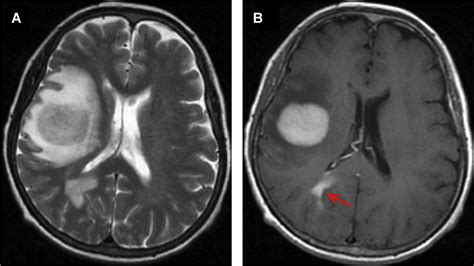

A standard Brain Neoplasm MRI protocol involves several different "sequences" or scan types. Each sequence is designed to highlight different biological features of the tissue. For example, T1-weighted images are excellent for anatomical detail, while T2-weighted and FLAIR (Fluid-Attenuated Inversion Recovery) images are highly sensitive to identifying edema or inflammation around a mass.

To improve the diagnostic accuracy, doctors often use a gadolinium-based contrast agent. When injected intravenously, this contrast material accumulates in areas where the blood-brain barrier is compromised, which is typical in many types of neoplasms. This "enhancement" helps doctors clearly delineate the tumor from healthy brain tissue.

Interpreting the Results